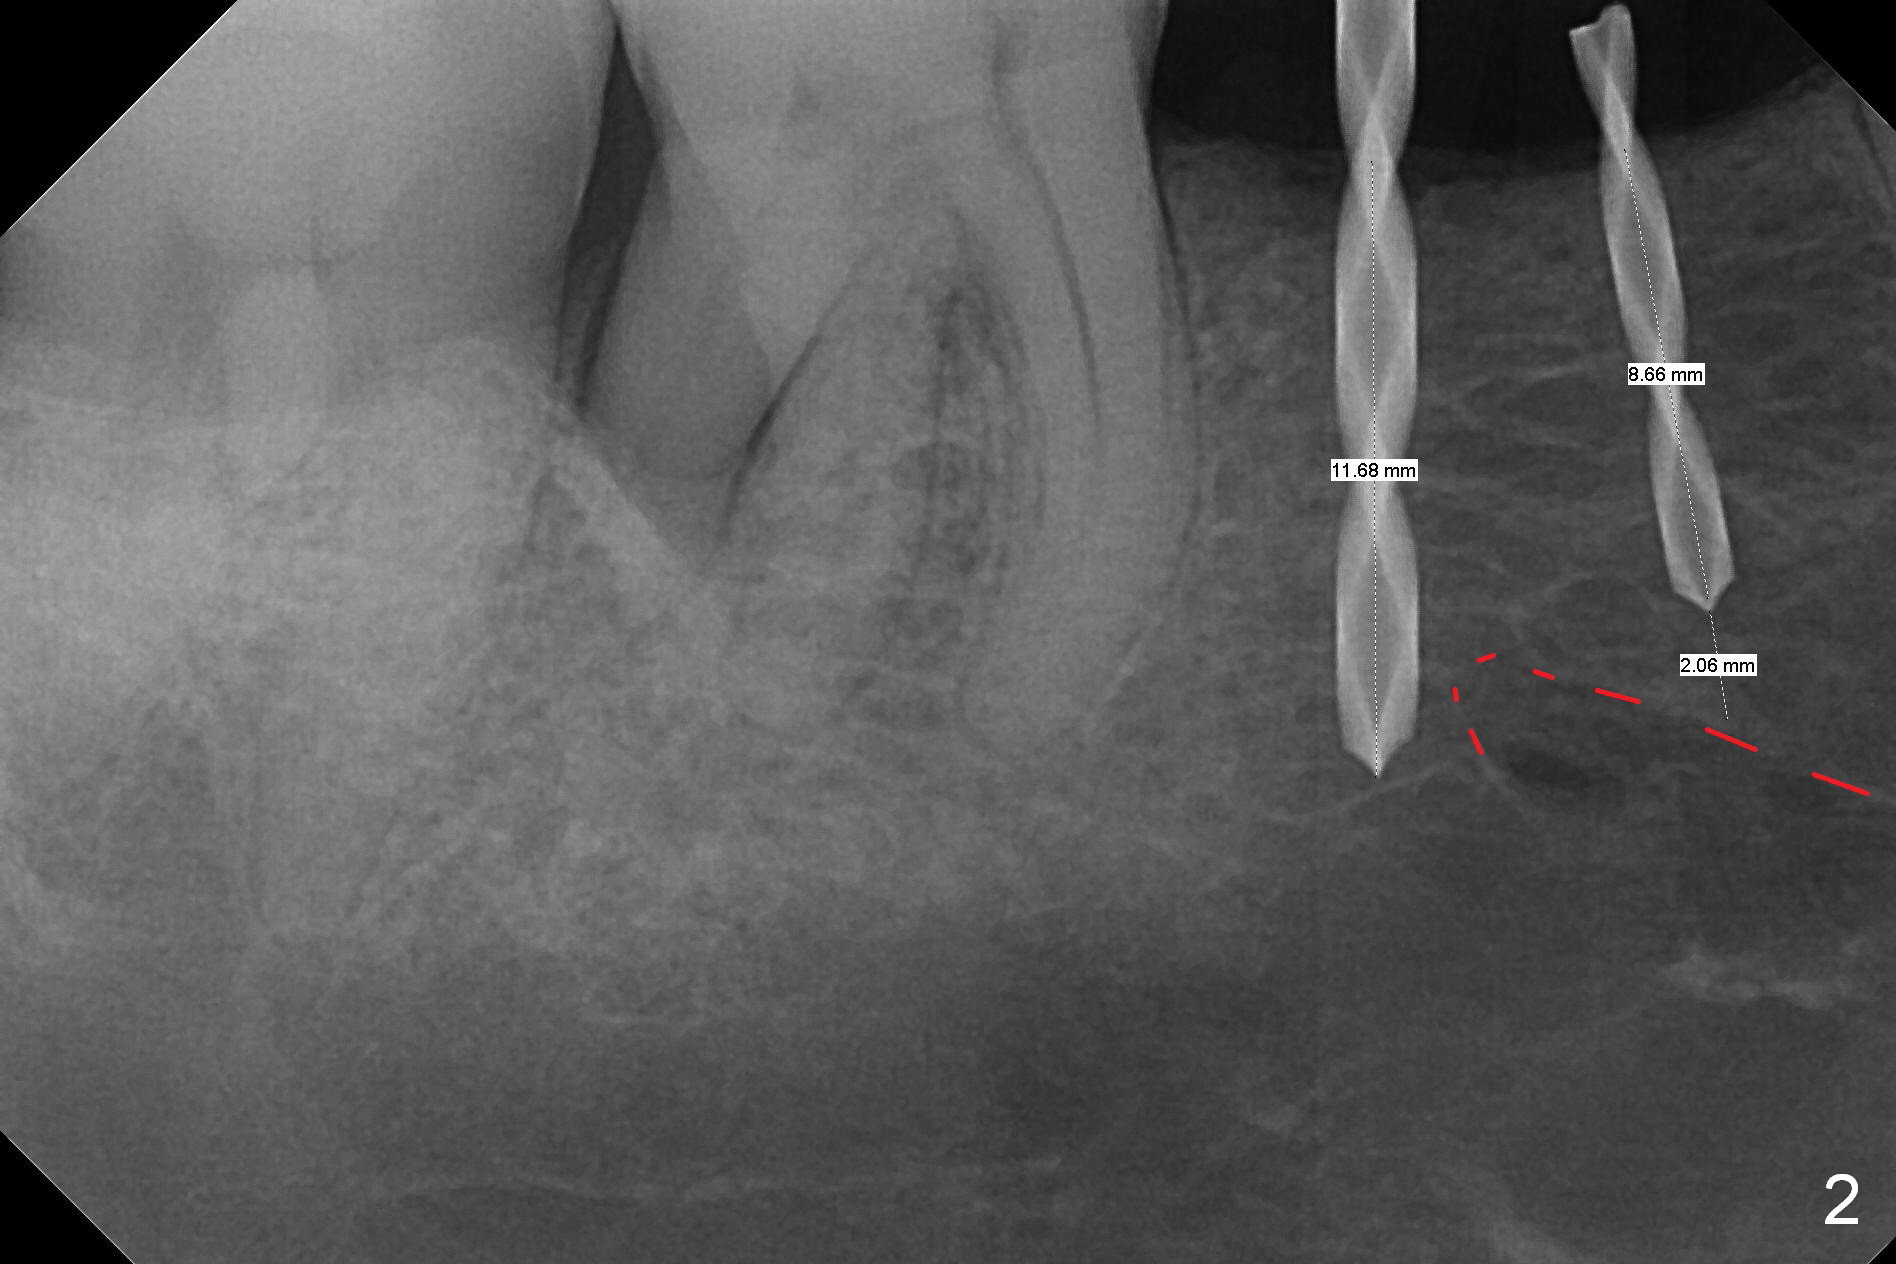

The wide mesiodistal space at #29 is most likely due to congenital missing permanent tooth (i.e., deciduous molar retention before extraction 34 years ago). The patient is now 62 years old. In fact the buccolingual width is not so narrow (Fig.1). After incision, the ridge is approximately 5 mm. Two osteotomies are established with 1.2 mm drill at 8 mm mesially and 1.5 mm one at 10 mm distally (Fig.2). The apparent approximation of the mesial osteotomy to the Mental Loop (red dashed line) is related to X-ray angulation, since there is 1-2 mm separation when two of 2x10(2) mm 1-piece implants are placed (Fig.3,4). Insertion torques of the mesial and distal implants are less than 25 and 15 Ncm, respectively. In fact bone graft is placed around the distolingual root of the tooth #30 after calculus removal (Fig.4 <). Following reduction of the abutments, periodontal dressing is applied locally. The dressing dislodged 13 days postop (Fig.5). A provisional is going to be fabricated 4 weeks postop when the wound heals (Fig.6). No bone loss is observed 4 months postop (Fig.7).